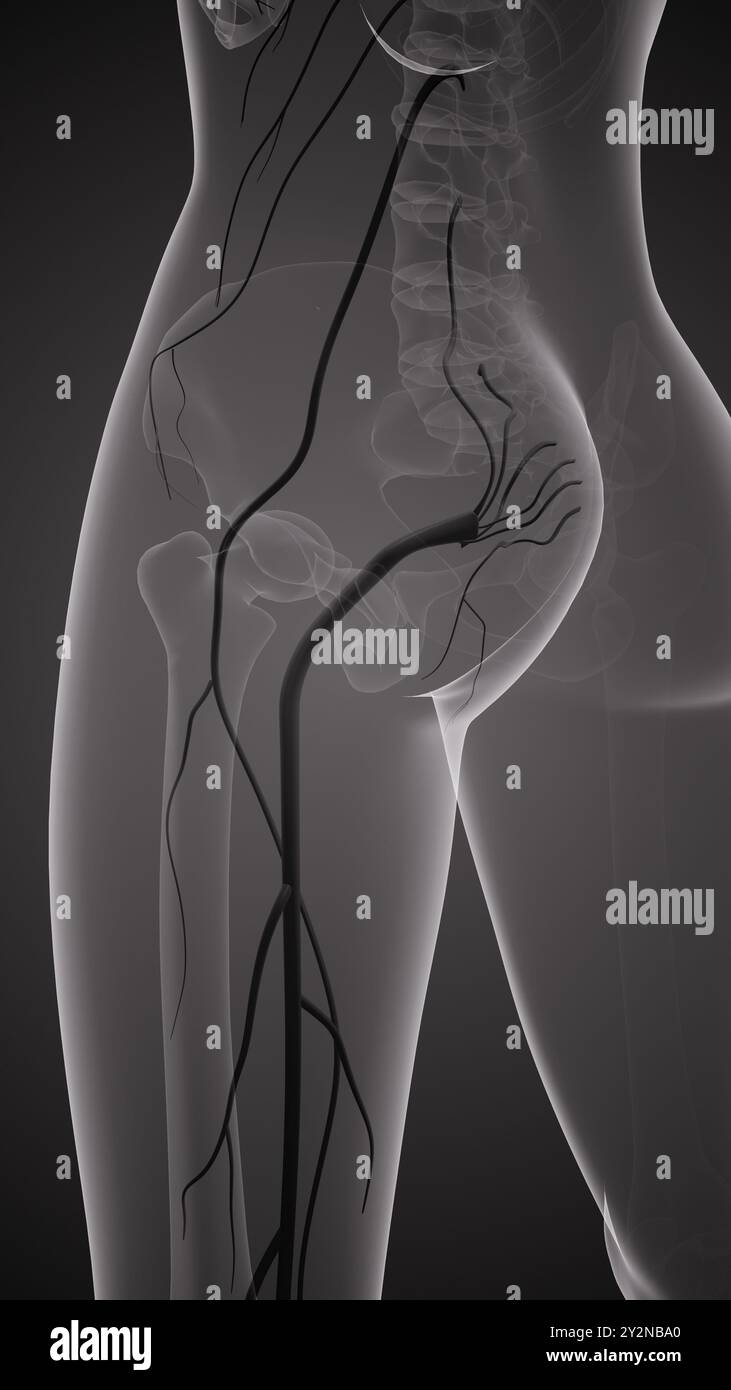

Douleur du nerf sciatique dans le bas du dos Banque D'Imageshttps://www.alamyimages.fr/image-license-details/?v=1https://www.alamyimages.fr/douleur-du-nerf-sciatique-dans-le-bas-du-dos-image621272456.html

Douleur du nerf sciatique dans le bas du dos Banque D'Imageshttps://www.alamyimages.fr/image-license-details/?v=1https://www.alamyimages.fr/douleur-du-nerf-sciatique-dans-le-bas-du-dos-image621272456.htmlRF2Y2NBA0–Douleur du nerf sciatique dans le bas du dos

Douleur du nerf sciatique dans le bas du dos Banque D'Imageshttps://www.alamyimages.fr/image-license-details/?v=1https://www.alamyimages.fr/douleur-du-nerf-sciatique-dans-le-bas-du-dos-image621272446.html

Douleur du nerf sciatique dans le bas du dos Banque D'Imageshttps://www.alamyimages.fr/image-license-details/?v=1https://www.alamyimages.fr/douleur-du-nerf-sciatique-dans-le-bas-du-dos-image621272446.htmlRF2Y2NB9J–Douleur du nerf sciatique dans le bas du dos

Douleur du nerf sciatique dans le bas du dos Banque D'Imageshttps://www.alamyimages.fr/image-license-details/?v=1https://www.alamyimages.fr/douleur-du-nerf-sciatique-dans-le-bas-du-dos-image621272450.html

Douleur du nerf sciatique dans le bas du dos Banque D'Imageshttps://www.alamyimages.fr/image-license-details/?v=1https://www.alamyimages.fr/douleur-du-nerf-sciatique-dans-le-bas-du-dos-image621272450.htmlRF2Y2NB9P–Douleur du nerf sciatique dans le bas du dos